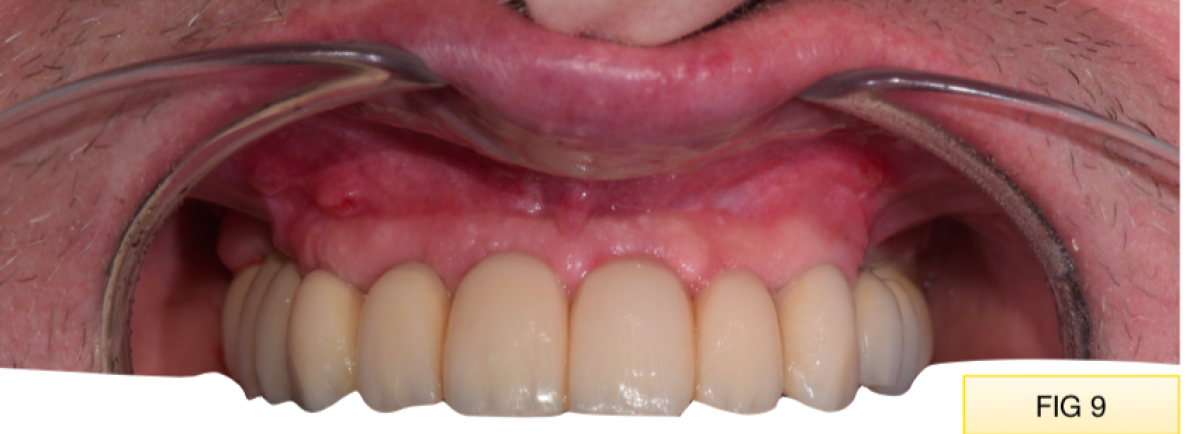

At the end the screwed temporary restoration is fixed with metal-metal cement at the abutments in oral cavity to ensure the passivation. FIG 9